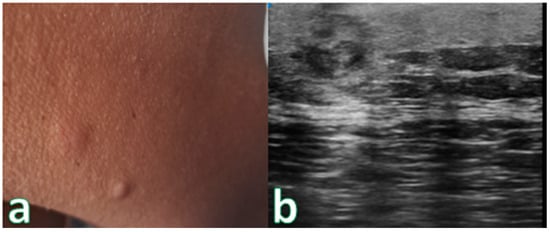

Figure 3. (a) Reddish nodular skin lesion without signs of flogisis in the anterior region of the right leg. (b) Examination performed with a very high-frequency ultrasound probe at 50 MHz showing iso-hypoechoic lesion with irregular and hyperechoic margins infiltrating the epidermis and the subepidermal layer highlighted with dashed blue line. Final pathologic assessment revealed to be a B-Cell Lymphoma.

Cancers 16 02456 g003

Figure 4. (a) Nodular skin lesion without signs of flogisis in the right deltoid region. (b) Exam performed with a very high-frequency ultrasound probe at 50 MHz: Iso-hypoechoic lesion with irregular and hyperechoic margins infiltrating the epidermis and the subepidermal layer. Pathologic Assessment revealed B-Cell Lymphoma.

Cancers 16 02456 g004

Single or multiple hypoechoic nodules (Figure 2) with focal epidermal–subepidermal involvement, featuring regular margins without peripheral infiltration, were typical of B-cell lymphoma (Figure 3 and Figure 4).